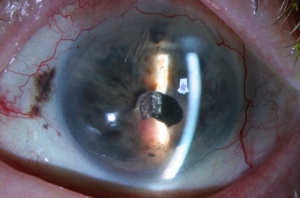

Cilary Body Melanoma

Melanomas of the ciliary body are often relatively large when they present. They have the same characteristics as choroidal melanoma but more frequently have a sentinel vessel (dilated tortuous episcleral vessel overlying the tumor). Additionally, these tumors are more likely to present with anterior displacement of the lens-iris diaphragm and a secondary angle closure glaucoma.